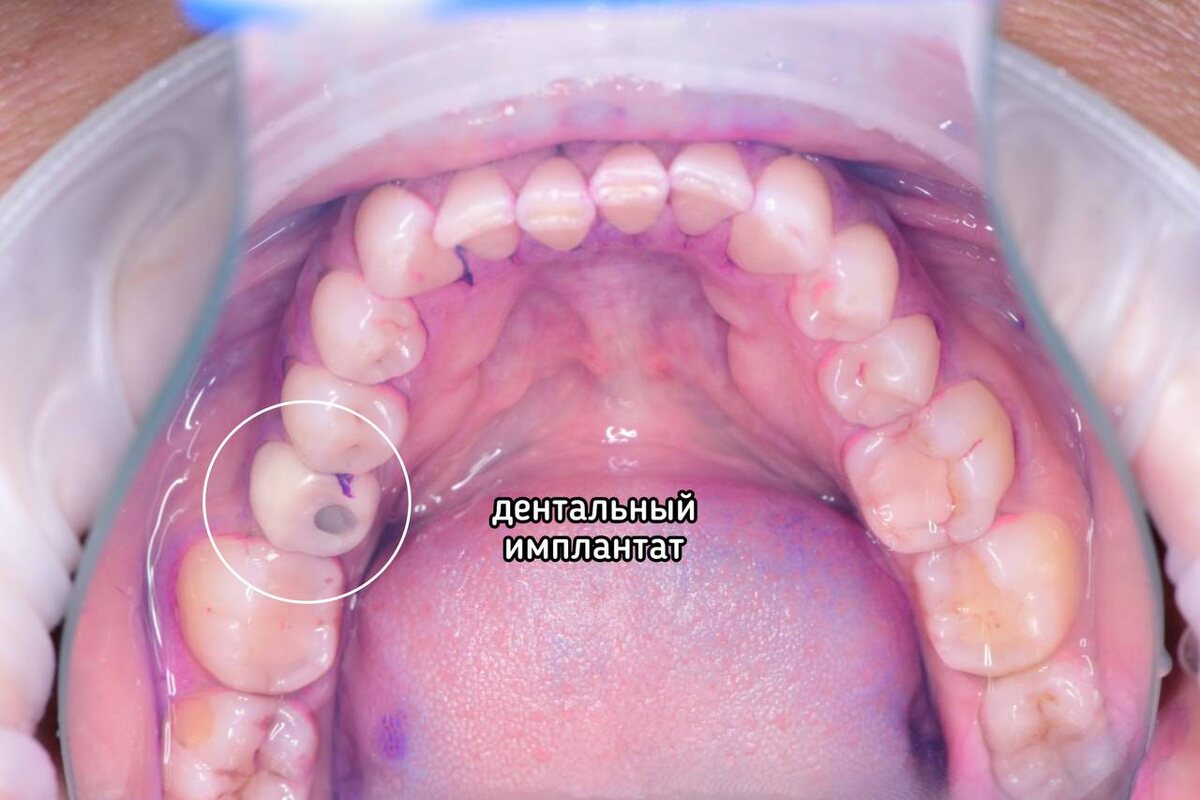

У Елены имеется один дентальный имплантат — это зуб 3.5. С ним все в порядке, он состоятелен, отторжения нет👇

С имплантатом пациентки все в порядке